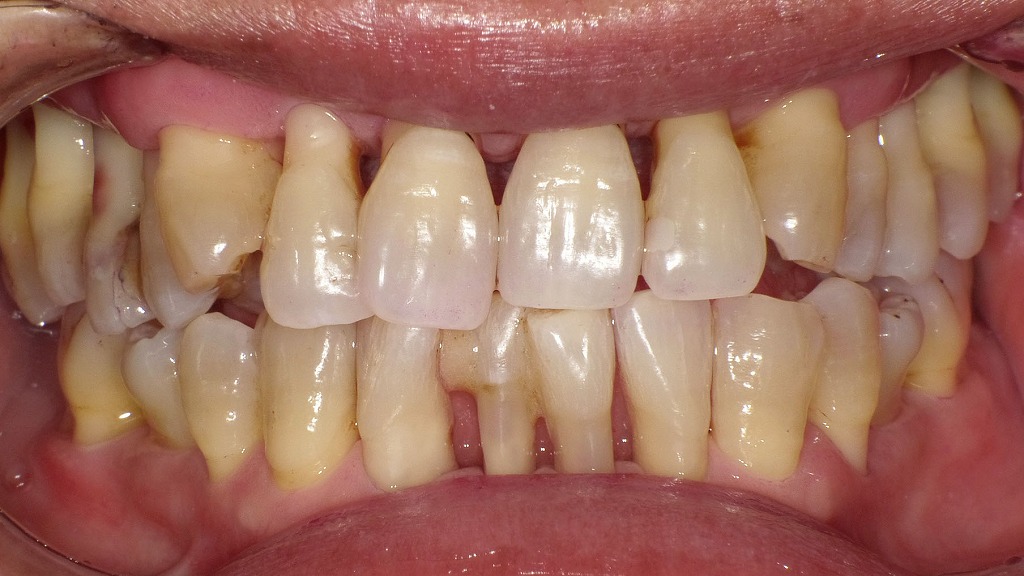

👀正面観

重度歯周病の治療を行った結果、炎症が改善し歯ぐきの腫れが引いたことで、歯肉退縮が明確に認められます。現在はプラークコントロールが良好で、清掃状態は安定しています。

下顎前歯部には動揺抑制を目的とした暫間固定を行い、定期的なプロフェッショナルクリーニングにより、歯周組織の健康維持を図っています。